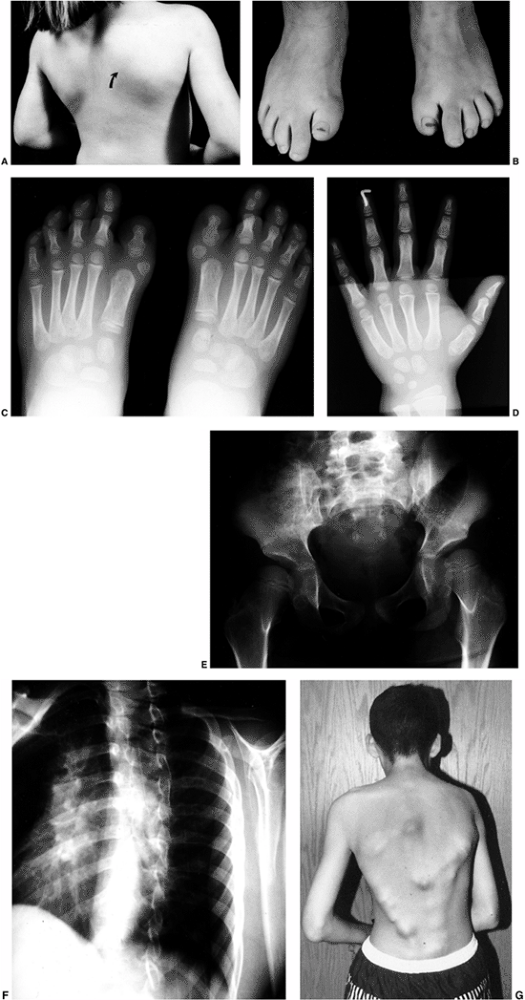

although occasionally the dynamic type may not become apparent until

later in infancy, when relentless enlargement occurs (Fig. 10.7).

![]() |

Figure 10.7 A 2-and-a-half-year-old girl with progressive macrodactyly of both feet, with macrodystrophica-lipomatosa. A:

There is significant plantar hypertrophy, resulting in hyperextension of the digits, and there is marked asymmetry in the digital enlargement. B, C: The plain radiographs demonstrate soft-tissue enlargement, as well as underlying bony enlargement. D: The magnetic resonance imaging demonstrates overgrowth of essentially all the elements of the digit, particularly the fibroadipose tissue typically seen in macrodystrophica-lipomatosa. |